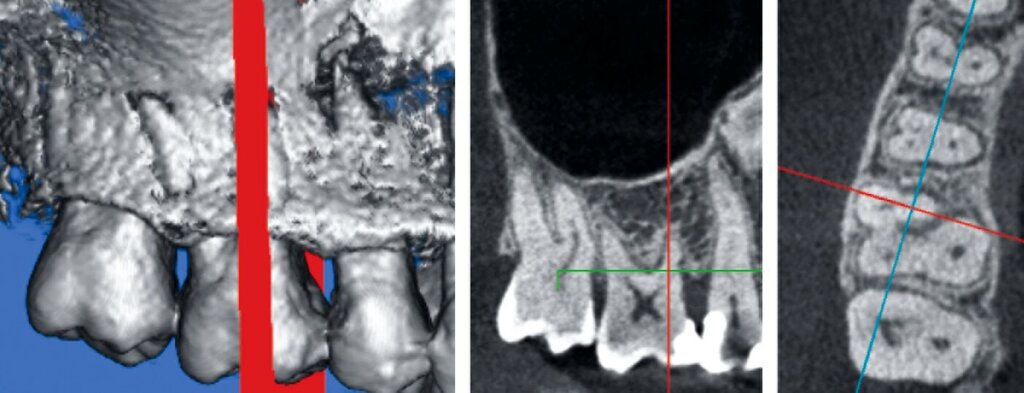

Regenerative Therapie von Molaren mit kombiniert horizontalem und vertikalem Knochenverlust

Bisher gibt es nur wenige Informationen über die Ergebnisse der regenerativen Therapie bei Molaren, die durch eine Kombination von Furkations- und intraossären Defekten kompromittiert sind, obwohl derartige Situationen in der klinischen Praxis häufig anzutreffen sind. In einer retrospektiven Fallserie wurden nach einem Jahr bei 100 Prozent der Oberkiefermolaren und 92 Prozent der Unterkiefermolaren Verbesserungen – definiert als Zahnerhalt, Verringerung des horizontalen und des vertikalen Furkationsgrades, Reduktion der Sondierungstiefen und Zunahme des klinischen Attachmentniveaus – berichtet [Cortellini et al., 2020]. Bei Molaren mit Hypermobilität zu Beginn der Behandlung wurden diese positiven Effekte nicht beobachtet. Eine Verbesserung des vertikalen Furkationsgrades wurde bei 87,5 Prozent der Oberkiefermolaren und bei 84,6 Prozent der Unterkiefermolaren beobachtet. Die Ein-Jahres-Verbesserungen konnten über die Nachbeobachtungszeit von drei bis 16 Jahren beibehalten werden. Diese Ergebnisse wurden in Fällen mit einem koronal zum Furkationseingang befindlichen interdentalen Knochenniveau und Gingivarand und Patienten mit guter Compliance und Mundhygiene erzielt.

2. Auswahl des Zahnes

Ein adäquater Zugang zum Operationsbereich und auch für die zukünftigen Mundhygienemaßnahmen ist äußerst wichtig. Molaren mit Grad-II-Furkationsdefekten (mandibulär und bukkal maxillär) sind Kandidaten, die für ein regeneratives Verfahren infrage kommen. Basierend auf der verfügbaren Evidenz sind interdentale Grad-II-Furkationsdefekte an Oberkiefermolaren deutlich weniger geeignet, höchstwahrscheinlich aufgrund des eingeschränkten Zugangs. Weitere lokale Charakteristika können Auswirkungen auf die Ergebnisse der regenerativen Furkationschirurgie haben. Zum Beispiel können ein dickerer Phänotyp und das Fehlen einer Weichgeweberezession die Heilung nach GTR-Verfahren positiv beeinflussen. Günstigere Ergebnisse sind an Stellen zu erwarten, an denen das verbleibende approximale Knochenniveau koronal zum Eingang beziehungsweise zum Dach des Furkationsdefekts liegt, verglichen mit solchen, bei denen das approximale Knochenniveau auf der Höhe oder apikal des Furkationseingangs liegt. Ein enger interradikulärer Abstand kann eine gründliche Defektinstrumentierung beeinträchtigen. Das Vorhandensein einer Wurzelkanalfüllung ist nicht per se eine Kontraindikation für die Furkationsregeneration – vorausgesetzt, es gibt keine Anzeichen für apikale pathologische Veränderungen.